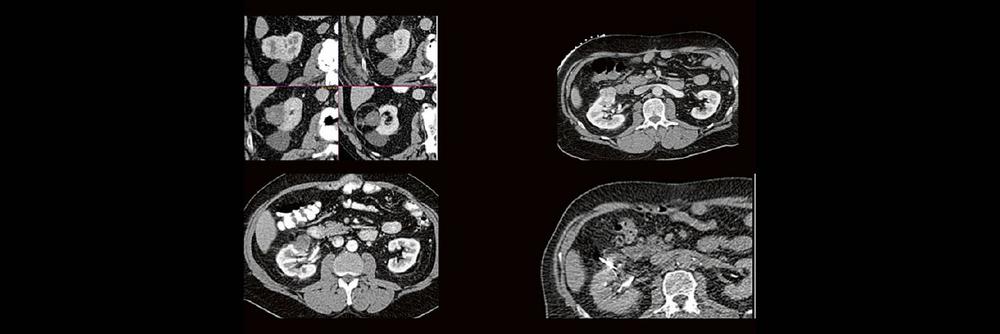

Die Anwendung von ablativen Verfahren hat sich in der klinischen Praxis etabliert. Nierentumoren bieten sich für den Einsatz von RFA und Mikrowelle an. Im Dietrich Bonhoeffer Klinikum Neubrandenburg blicken wir auf 15 Jahre Erfahrung mit mehr als 100 RFA/Mikrowellenablationen von Nierentumoren zurück. Im Vortrag werden die eigenen Erfahrungen und Ergebnisse vorgestellt.

Dabei wird auf die Indikationsstellung, Vorbereitung, Durchführung, Nachuntersuchungsintervall, Komplikationen und Erfolgsrate eingegangen.